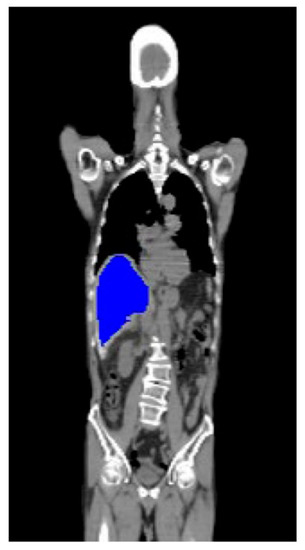

Automatic liver segmentation from 18F-FDG-PET-CT images is a highly crucial step in image preprocessing. To segment the hepatic areas, we leveraged semiautomated organ-contouring software to delineate the contour of the liver on the Digital Imaging and Communications in Medicine (DICOM) images. The tool is usually used in routine clinical radiotherapy planning to help radiologists confirm the location of cancer at which the radiation is aimed. We omitted the data outside the hepatic areas during model training and only adopted the CT and PET information within the liver areas (Figure A2).

Figure A2.

The liver 3D range is marked for training.